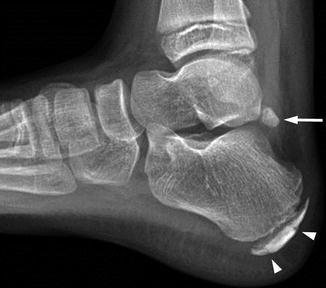

How could you tell the difference between a 5th MT base fracture in an adolescent and the normal anatomical accessory ossification centre?

Ossification centre is longitudinal, 5th MT base fractures are transverse

Arrow = normal apophysis, arrowheads are other ossification centres